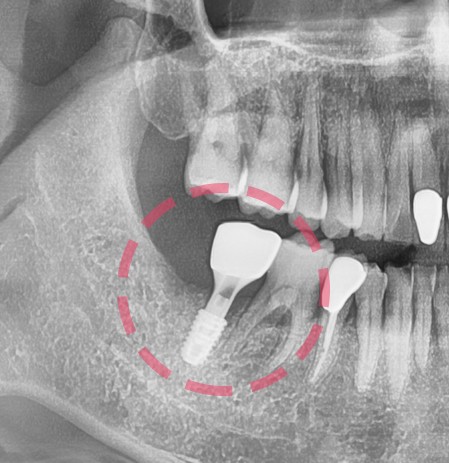

『3개월 경과, 크라운 시적』

자… 3개월이라는 시간이 소요 되었습니다.

사랑니 발치 이후 금연도 하셨고 무려 금주까지! 그래서 더 빨리 뼈가 아문 거 같습니다.

결국 치아 2개를 잃고, 새로운 치아 1개를 얻으셨네요.